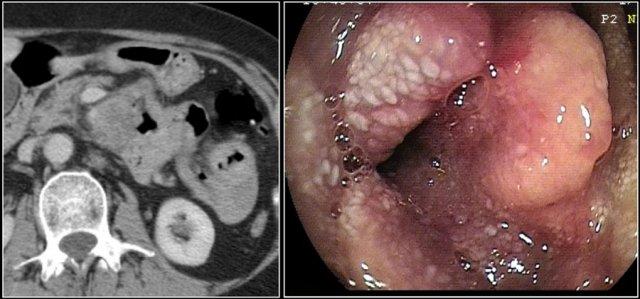

Các hình ảnh cho thấy một khối không đều ở đoạn gần hỗng tràng.

Mặc dù là khối phát triển theo chu vi với kích thước lớn, lòng ruột không bị tắc nghẽn.

Có một khối hạch bạch huyết tập hợp lớn giảm tỷ trọng ở mạc treo lân cận, phù hợp với di căn hạch bạch huyết hoại tử (hình dưới).

Kết quả giải phẫu bệnh xác nhận là ung thư biểu mô tuyến, nhưng các dấu hiệu này cũng có thể rất phù hợp với u lympho.

Đây là hình ảnh nội soi của khối u.

Đây là bệnh nhân có dày thành lan rộng ở đoạn gần hỗng tràng kèm giãn phình dạng túi phình.

Chẩn đoán hàng đầu trong danh sách chẩn đoán phân biệt của chúng tôi là u lympho, nhưng kết quả giải phẫu bệnh xác nhận là ung thư biểu mô tuyến.

Các đặc điểm gợi ý ung thư biểu mô tuyến là thâm nhiễm mỡ mạc treo (fat stranding) và di căn hạch bạch huyết.

Trong u lympho, thâm nhiễm mỡ ít gặp, nhưng di căn hạch bạch huyết vẫn xảy ra và thường có kích thước lớn hơn.